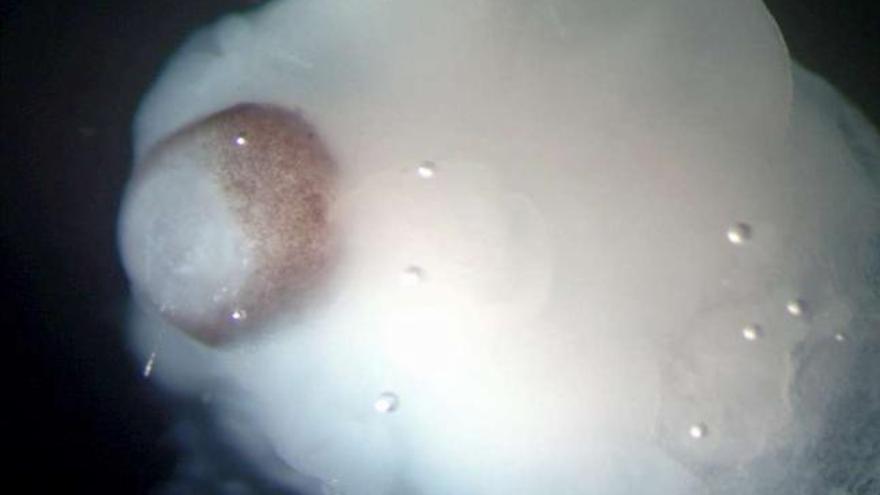

Pequeños cerebros del tamaño de un guisante que reflejan de forma bastante fiel las primeras etapas del desarrollo del cerebro humano. Es lo que ha logrado por primera vez en la historia médica un equipo de científicos europeos que han desarrollado cerebros humanos de cuatro milímetros de diámetro, a partir de células madre pluripotentes. Este hallazgo ayudará a profundizar en el estudio de las enfermedades neurológicas, según los resultados del estudio que publicó la revista científica Nature.

Estos órganos artificiales, fruto de una investigación conjunta de la Universidad de Bonn (Alemania) y el Instituto de Biotecnología Molecular de Viena (Austria), aportan importantes avances sobre el desarrollo del cerebro durante las etapas más tempranas y sus patologías.

"Este planteamiento puede superar algunas de las limitaciones que encontramos cuando experimentamos con el cerebro de los animales, ya que no comparte las mismas peculiaridades del cerebro humano", añadió el científico. Estos microcerebros, que incluyen la corteza cerebral que cubre los dos hemisferios, están formados por diferentes tejidos dispuestos en capas, cuya organización guarda muchas semejanzas con la de un cerebro en sus etapas más tempranas de desarrollo.